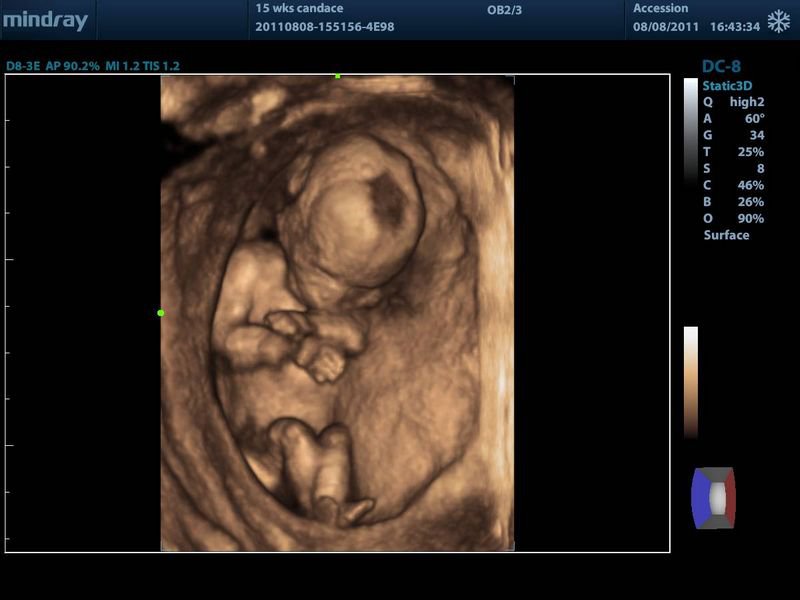

Методика ультразвукового исследования широко применяется в доказательной медицине для выявления большого спектра заболеваний и патологий органов и систем. Сегодня медицинский центр «Салюс» предлагает оценить все преимущества усовершенствованной формы данной технологии исследования – 3D УЗИ. Эта услуга приобретает в Керчи все большую популярность, особенно среди пар, ожидающих появление на свет малыша, ведь 3D-УЗИ обеспечивает возможность дополнить стандартный акушерский скрининг полным визуальным осмотром плода в высоком качестве цветного изображения.

Мы уже привыкли, что 3D/4D УЗИ – это УЗИ, чаще всего используемое для получения качественной фотографии или видеозаписи лица плода (baby face). Но неотъемлемым преимуществом данного метода исследования является возможность диагностировать наличие у ребенка каких-либо внешних дефектов и патологий, например таких, как:

Проведение 3D-ультразвука развеет все сомнения, позволив лично пересчитать пальчики на крошечных ножках и ручках, самостоятельно убедиться в отсутствии иных внешних дефектов. Именно подозрение на наличие данных пороков развития является одним из главных показаний к выполнению трехмерного УЗИ.

Благодаря 3D-ультразвуку специалисты имеют возможность оценить как весь плод, так и отдельно каждую его структуру в трех проекциях одновременно. Кроме того, 3D УЗИ позволяет более отчетливо видеть пол ребенка, что исключает диагностическую ошибку. Также к неоспоримым преимуществам 3D-УЗИ относится возможность рассмотреть мимику малыша, определяя, какие именно эмоции он испытывает. Это имеет огромное диагностическое значение, поскольку плохие эмоции, как правило, возникают на фоне страданий, испытываемых ребенком:

К минусам 3D УЗИ можно отнести лишь более продолжительное время исследования. Если обычное УЗИ проводится за 10-15 минут, то для того, чтобы сделать 3D УЗИ, требуется 45-50 минут. Также недостатком трехмерного ультразвука можно назвать ограничения, связанные со сроком беременности и с положением плода. Такое УЗИ рекомендуется сделать на 24-27 неделе беременности. После 30 недели плод обычно фиксируется спинкой к датчику, головка малыша опускается ниже в область таза, и рассмотреть его лицо больше нет возможности.

Во время проведения 3D УЗИ при беременности специалист предложит будущим родителям взять на память цифровую фотографию их малыша и видеоклип на CD/DVD, который станет первым в семейном архиве напоминанием о счастливом времени ожидания рождения крохи на свет.